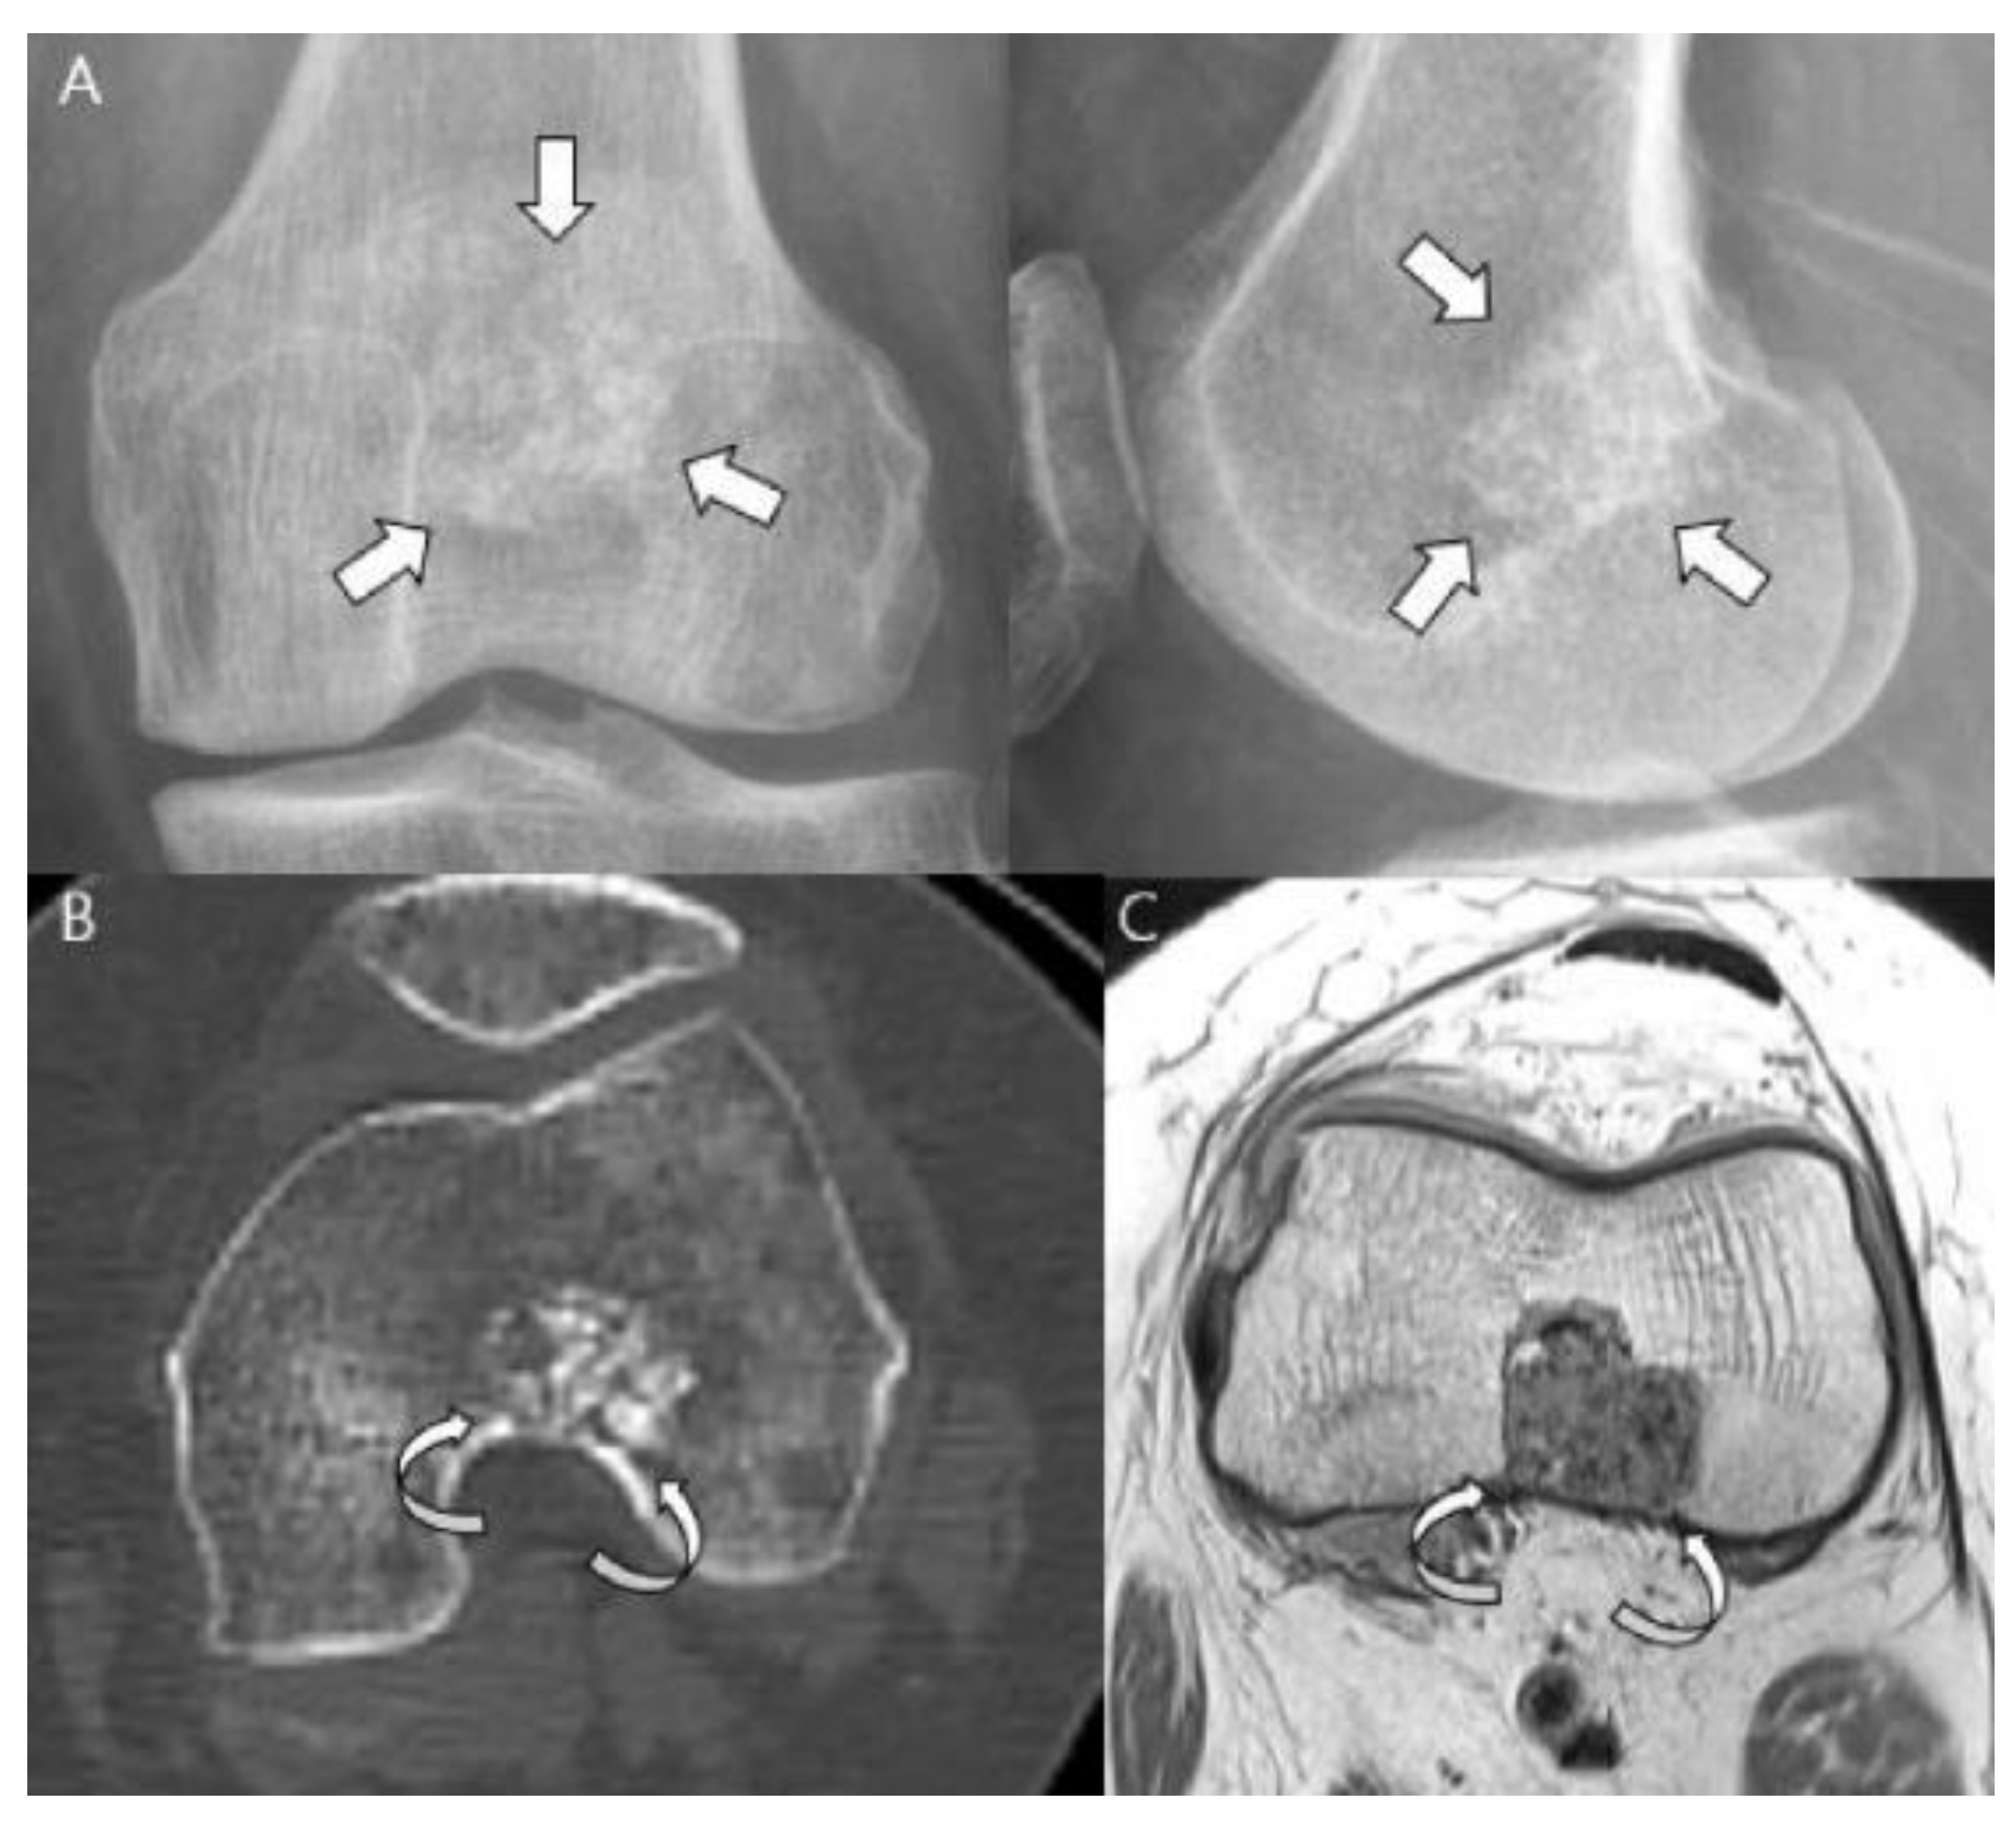

- Littrell, L.A.; Wenger, D.E.; Wold, L.E.; Bertoni, F.; Unni, K.K.; White, L.; Kandel, R.; Sundaram, M. Radiographic, CT, and MR Imaging Features of Dedifferentiated Chondrosarcomas: A Retrospective Review of 174 De Novo Cases. Radiographics 2004, 24, 1397–1409. [Google Scholar] [CrossRef]

- Saifuddin, A.; Mann, B.; Mahroof, S.; Pringle, J.; Briggs, T.; Cannon, S. Dedifferentiated chondrosarcoma: Use of MRI to guide needle biopsy. Clin. Radiol. 2004, 59, 268–272. [Google Scholar] [CrossRef]